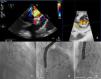

Surgical replacement of the mitral valve with a biologic prosthesis (31 mm Carpentier Edwards) was performed. Four months later, he was admitted for symptomatic hemolytic anemia (hemoglobin 9 g/dl, high lactate dehydrogenase and undetectable haptoglobin). Transesophageal echocardiography (TEE) showed severe antero-lateral paraprosthetic regurgitation (Figure 1A and B). Reoperation was proposed and refused by the patient. For this reason, and also because of his high surgical risk, it was decided to perform percutaneous paravalvular leak (PVL) closure.

The procedure was performed under general anesthesia, via the left femoral vein under fluoroscopic and TEE guidance. After transseptal puncture, a NuMED Tyshak II 12 mm×40 mm balloon was inflated at low pressure until complete closure was achieved and used to assess the dimension of the leak and choose the appropriate device. Two 7F sheaths (AGA Medical Corporation) were advanced across the mitral leak and an Amplatzer Vascular Plug III was deployed (Figure 1C) but still attached to the delivery cable. As the second sheath was occlusive (Figure 1D), it was decided to place a round device, an 8/6 mm Amplatzer Duct Occluder (Figure 1E). Only residual paraprosthetic regurgitant flow persisted and both devices were released. There was significant clinical improvement.

TEE revealed severe paraprosthetic regurgitation in an anterior position, close to the previously implanted devices (Figure 2B). Only one of the two devices was identified. Fluoroscopy confirmed embolization of the Amplatzer Duct Occluder to the left femoral artery (Figure 2A). Percutaneous removal was attempted but was unsuccessful and surgical removal was performed.

Fluoroscopy showing embolization of the Amplatzer Duct Occluder to the left femoral artery (A). Transesophageal echocardiography (TEE) revealed severe paraprosthetic regurgitation (B). An Amplatzer Muscular VSD Occluder was implanted near to the previous device (C). Three months later, TEE showed moderate paraprosthetic regurgitation (D). The devices were surgically removed (E).

Because the patient remained unwilling to undergo surgical correction, after a multidisciplinary discussion, a redo percutaneous closure was tried as a final option. The leak was crossed anteroseptally with a 280 cm, 0.035″ hydrophilic Terumo guidewire. As it was difficult to cross the leak with the 45° curve Amplatzer 7F sheath an arteriovenous loop was performed, snaring the wire in the aorta, through the femoral artery. An 8 mm Amplatzer Muscular VSD Occluder was implanted near to the previously implanted Amplatzer Vascular Plug III (Figure 1C). TEE at the end of the procedure showed only mild to moderate paraprosthetic regurgitation. There was prompt favorable clinical evolution.

Three months later, the patient again developed HF symptoms and hemolytic anemia. TTE (Figure 2D) showed the two devices in an anterior-lateral position and moderate paraprosthetic regurgitation. The mitral prosthetic valve was functioning normally.